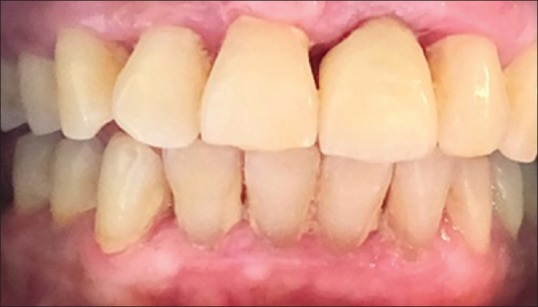

The crestal bone levels were evaluated around the implant at baseline, after 6 and 8 months (postloading) using CBCT. The palatal and labial measurements were done on the sagittal section, while mesial and distal measurements were done on the tangential or coronal sections in the CBCT using measuring tools. The CBL was indicated by a negative value (−) and bone growth was indicated by a positive (+) value. The second-stage surgery was performed after 6 months of implant placement. All the observations relevant to each parameter, i.e., RFA values and crestal bone levels which were recorded at baseline, 6 and 8 months were expressed in the form of mean, standard deviations, and maximum and minimum scores. Unpaired t-test was used to make intergroup comparisons, while one-way ANOVA F-test was used to make intragroup comparisons. Standard prosthetic procedure were used for the fabrication of prosthesis [Figure 5], and implant protected occlusion was given [Figure 6].

Figure 5.

Abutment in place

Figure 6.

Final prosthesis in place